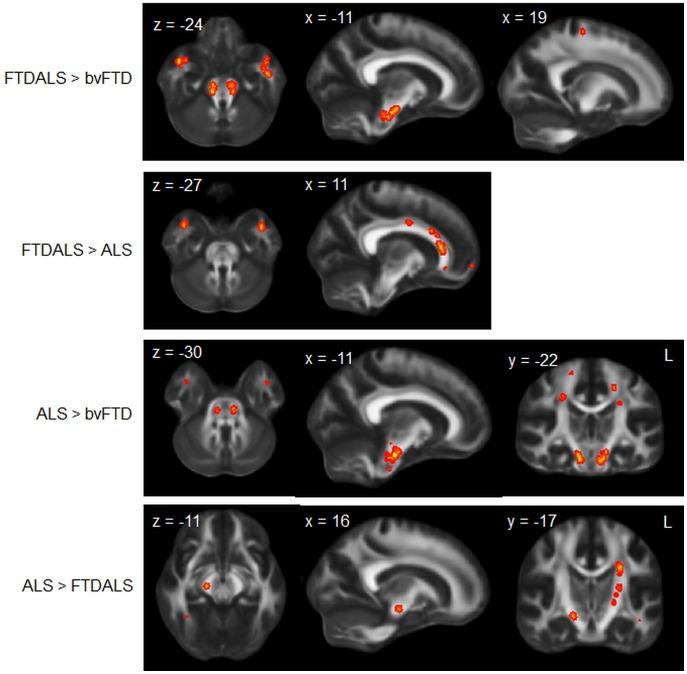

There is increasing evidence that amyotrophic lateral sclerosis (ALS) and frontotemporal dementia (FTD) lie on a clinical, pathological and genetic continuum with patients of one disease exhibiting features of the other. Nevertheless, to date, the underlying grey matter and white matter changes across the ALS-FTD disease continuum have not been explored. In this study fifty-three participants with ALS (n = 10), ALS-FTD (n = 10) and behavioural variant FTD (bvFTD; n = 15) as well as controls (n = 18), underwent detailed clinical assessment plus structural imaging using voxel-based morphometry (VBM) and diffusion tensor imaging (DTI) analysis of magnetic resonance brain imaging to examine grey and white matter differences and commonalities across the continuum. Importantly, patient groups were matched for age, education, gender and disease duration. VBM and DTI results showed that changes in the ALS group were confined mainly to the motor cortex and anterior cingulate as well as their underlying white matter tracts. ALS-FTD and bvFTD showed widespread grey matter and white matter changes involving frontal and temporal lobes. Extensive prefrontal cortex changes emerged as a marker for bvFTD compared to other subtypes, while ALS-FTD could be distinguished from ALS by additional temporal lobe grey and white matter changes. Finally, ALS could be mainly distinguished from the other two groups by corticospinal tract degeneration. The present study shows for the first time that FTD and ALS overlap in anterior cingulate, motor cortex and related white matter tract changes across the whole continuum. Nevertheless, frontal and temporal atrophy as well as corticospinal tract degeneration emerged as marker for subtype classification, which will inform future diagnosis and target disease management across the continuum.

越来越多的证据表明,肌萎缩侧索硬化症(ALS)和额颞叶痴呆(FTD)在临床、病理和遗传上存在连续性,一种疾病的患者表现出另一种疾病的特征。尽管如此,迄今为止,ALS-FTD 疾病连续体中的潜在灰质和白质变化尚未得到探索。在这项研究中,53 名参与者包括 ALS(n=10)、ALS-FTD(n=10)和行为变异型额颞叶痴呆(bvFTD;n=15)以及对照组(n=18),他们接受了详细的临床评估以及结构成像,包括基于体素的形态学(VBM)和磁共振脑成像的弥散张量成像(DTI)分析,以检查连续体中的灰质和白质差异和共性。重要的是,患者组在年龄、教育程度、性别和疾病持续时间方面相匹配。VBM 和 DTI 结果表明,ALS 组的变化主要局限于运动皮层和前扣带回及其下的白质束。ALS-FTD 和 bvFTD 显示出广泛的灰质和白质变化,涉及额叶和颞叶。与其他亚型相比,广泛的前额叶皮层变化成为 bvFTD 的标志物,而 ALS-FTD 可以通过额外的颞叶灰质和白质变化与 ALS 区分开来。最后,皮质脊髓束变性可将 ALS 主要与其他两组区分开来。本研究首次表明,FTD 和 ALS 在整个连续体中存在前扣带回、运动皮层和相关白质束变化的重叠。然而,额叶和颞叶萎缩以及皮质脊髓束变性作为亚型分类的标志物出现,这将为连续体中的未来诊断和靶向疾病管理提供信息。